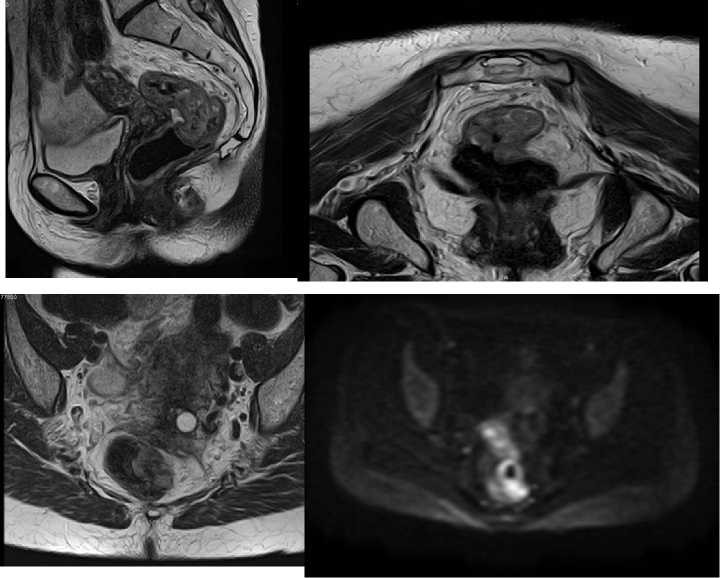

Imágenes de resonancia magnética